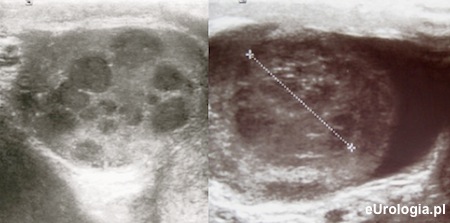

USG moszny jest nieinwazyjnym badaniem wykonywanym w przypadku podejrzenia jakiejkolwiek patologii w obrębie moszny. Badanie jest niebolesne i polega na ultrasonograficznej ocenie jądra, najądrza i powrózka nasiennego. Badanie USG jądra wykonywane jest głowicą liniową i jest złotym standardem w diagnostyce obrazowej nowotworów jądra. Badanie USG w diagnostyce nowotworów jądra charakteryzuje się blisko 100% czułością.

Fot. Przykłady guzów jądra w badaniu USG.